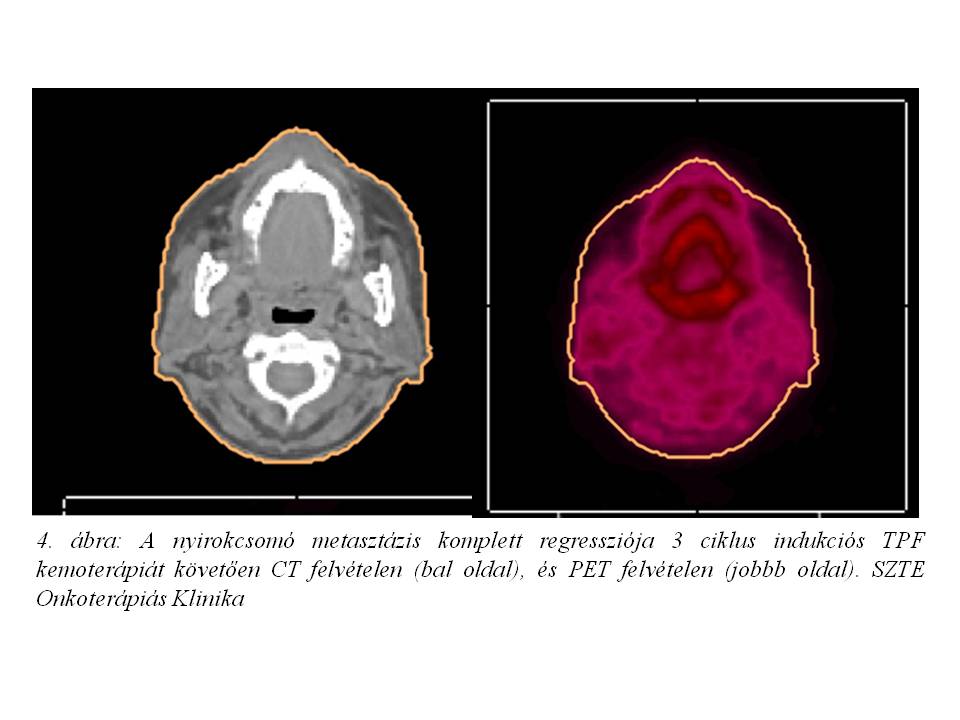

Esetismertetés: Jelenleg 52 éves, 30 éve dohányzó (napi 10 szál cigaretta), alkoholt nem fogyasztó, 20 évvel ezelőtt gyomorfekély miatt műtéten átesett, jelenleg hypothyreosissal kezelt nőbeteg esetét ismertetjük. A beteg 2014 júniusában jelentkezett fül-orr-gégészeten két éve tartó gombócérzés, időnként tapasztalt nyelési nehezítettség és fájdalom, a nyak bal oldalán 1 éve észlelt fájdalmatlan, kemény csomó, 2 hónap alatti 10 kg testsúlyvesztés, és 1 hónapja tartó, antibiotikus kezelésre nem szűnő, a bal fül felé sugárzó torokfájdalom miatt. Fizikális vizsgálat során a fejbiccentő izom elülső széle mentén a parajugularis régióban 2,5 cm átmérőjű, mobilis, ép bőrrel fedett nyirokcsomót észleltek. Rhino-pharyngo-laryngo-fiberoscopia során a bal oldali sinus piriformisban U-alakú, egyenetlen szövetszaporulat és nyálpangás igazolódott. Nyaki és mellkasi CT vizsgálat a hypopharynx régióban, a baloldali sinus piriformist kitöltő, a kontrasztanyagot homogénen és intenzíven halmozó, 20 x 14 x 20 mm nagyságú, a középvonalat meg nem haladó térszűkítő elváltozást, ebben a magasságban baloldalon a vena jugularis internát komprimáló, 20 mm átmérőjű, nekrotikus bennékű metasztázist, valamint a C.II csigolya szintjében dorsalisan egy 2 cm-es, patológiás szerkezetű nyirokcsomót írt le (1. ábra, 2. ábra). A tüdőkben metasztázisra utaló eltérés nem volt (T3 N2 cM0 stádium). Laryngomicroscopia során a bal oldali pharyngo-és aryepiglotticus redőn, illetve a sinus piriformis medialis falán elhelyezkedő teriméből szövettani mintavétel történt, mely közepesen differenciált laphámcarcinomát igazolt. Indukciós TPF kemoterápiát (docetaxel-cisplatin-5-fluorouracil) indítottunk, melynek 1. ciklusát követően a tapintható nyirokcsomó metasztázis eltűnt, a beteg nyelési fájdalmai megszűntek. A kemoterápia harmadik ciklusát követően fül-orr-gégészeti vizsgálat során makroszkópos tumor nem volt látható, az elvégzett PET/CT vizsgálat során FDG-avid malignitás nem igazolódott (3. ábra, 4. ábra). Jelenleg a beteg definitív sugárkezelését végezzük.